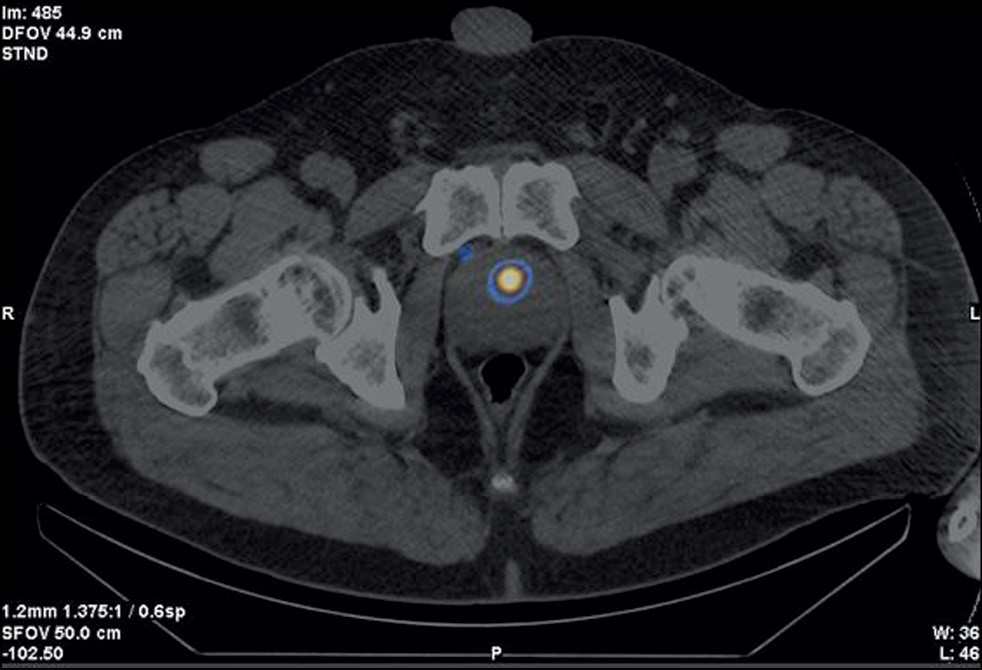

Case report 7

Patient M., 6 years old, had an increased PSA level of 6.8 ng/mL and underwent a multifocal prostate biopsy at a local clinic. The diagnosis was confirmed morphologically as adenocarcinoma, Gleason 6 (3 + 3), based on data from the transitory zone of the right prostate lobe. Adenocarcinoma elements were not found in other prostate biopsy specimens. Considering MRI evidence of changes in the same zone, implantation with 30 125I sources with a 32-cm3 volume was proposed.

SPECT/CT with 99mTc-HYNIC-PSMA revealed diffuse focal RP accumulation under the base of the bladder. PET/CT with 68Ga-PSMA-11 was additionally performed to more accurately visualize prostate lesions. PET/CT revealed multiple sites of RP accumulation in the prostate gland, indicating that the tumor was multifocal (Figure 8). Implantation planning was adjusted to include the total volume of the prostate gland (78 cm3) using 90 125I microsources (instead of preliminary 30 microsources).

Fig. 8. Patient M., 69 years old, PET/CT with 68Ga-PSMA-11: Sites of radiopharmaceutical accumulation in the prostate gland, multifocal tumor.

On February 25, 2022, implantation was performed for the total volume of the prostate gland. The initial prostate volume for brachytherapy was 32 cm3. PET/CT revealed a volume of 72 cm3 for implantation. The PSA level decreased to 0.31 ng/mL within a year after brachytherapy.